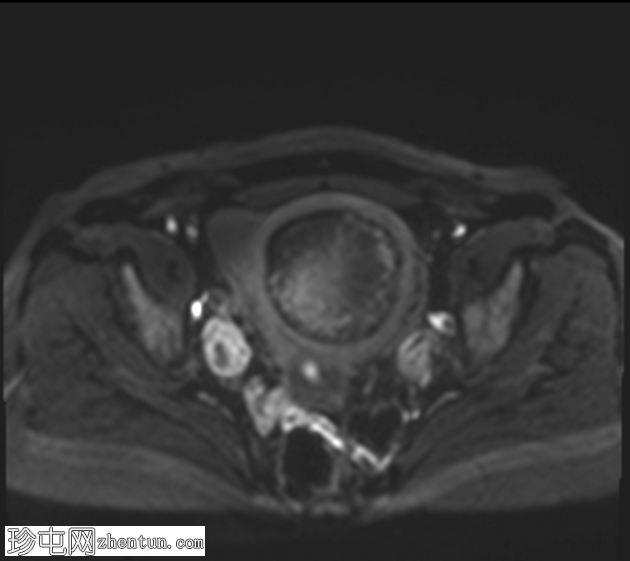

轴位T2加权像

脂肪抑制

子宫前壁可见一边界清晰的壁内病灶,大小约7.8 × 7 × 6.8 cm。脂肪抑制T1加权像呈弥漫性高信号,T2加权像呈高信号伴低信号环,无扩散受限及对比增强。

此外,可见一个2厘米的带蒂浆膜下肌瘤,以及较小的肌壁内和浆膜下肌瘤;所有肌瘤均呈均匀强化。

盆腔内可见少量游离液体,可能为生理性。